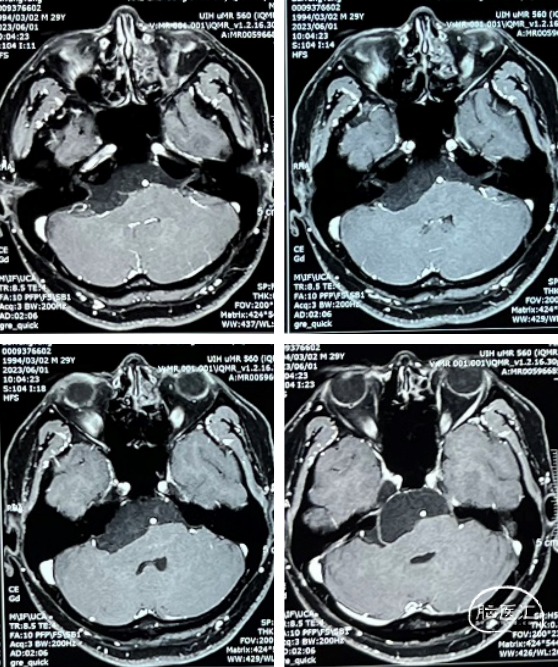

术后MRI